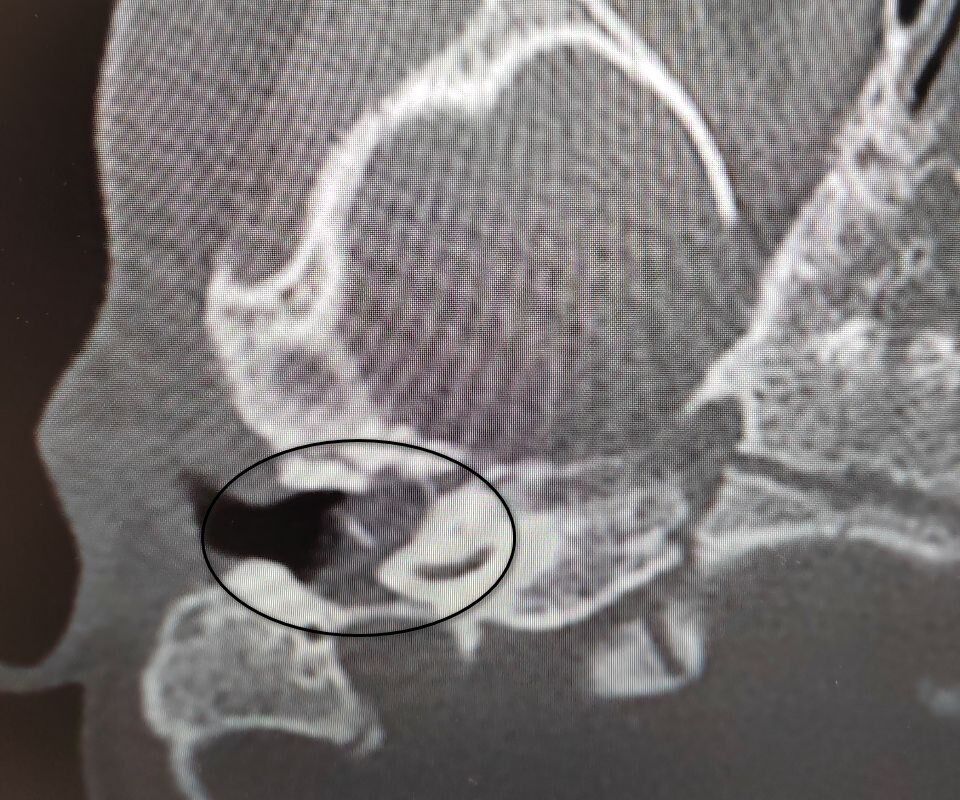

Девочка поступила в оториноларингологическое отделение больницы с хроническим гнойным средним отитом и подозрением на врожденную холестеатому барабанной полости — кистозное патологическое образование в среднем ухе. Врачи отметили, что подобное заболевание крайне редко диагностируется у детей в столь раннем возрасте.

«Холестеатома опасна тем, что может привести к рецидивирующему гноетечению и разрушению структур среднего уха, отвечающих за слух», — пояснили в пресс-службе ведомства.

После обследования и подтверждения диагноза пациентку направили на операцию, в ходе которой хирурги удалили у нее холестеатому, провели декомпрессию лицевого нерва и восстановили механизм звукопроведения.